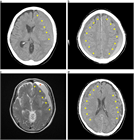

急性硬膜下血腫

1. 頭部外傷受傷直後から片麻痺等の神経症状や意識障害が持続する場合には、急性硬膜下血腫の存在を想起し呼吸・循環管理を行いつつ速やかに頭部CT撮影を行い診断する。

1. 抗血栓薬内服中の高齢者では軽微な外傷でも受傷することがあり、急速な意識障害の進行や亜急性の経過をとることもあり注意を要する。